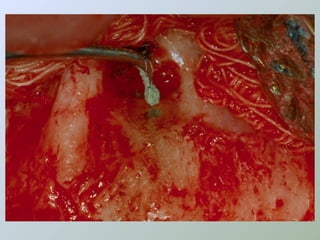

Deve-se observar, também, se não há

anomalias anatômicas como: rebarbas,

intercanais, canais acessórios ou fraturas

radiculares a este nível, podendo-se

utilizar solução esterilizada de azul-de-

metileno a 2%, para identificação destas

situações (DEL RIO, 1996) e, mesmo ainda

se ocorre uma infiltração apical em

cavidade para a obturação retrógrada.

(BERNARDINELLI et al., 1994)

Preparo e obturação apical

Indicado em casos de

selamento apical

inadequado

• Fresas

• Pontas ultra-sônicas

• Limas endodônticas